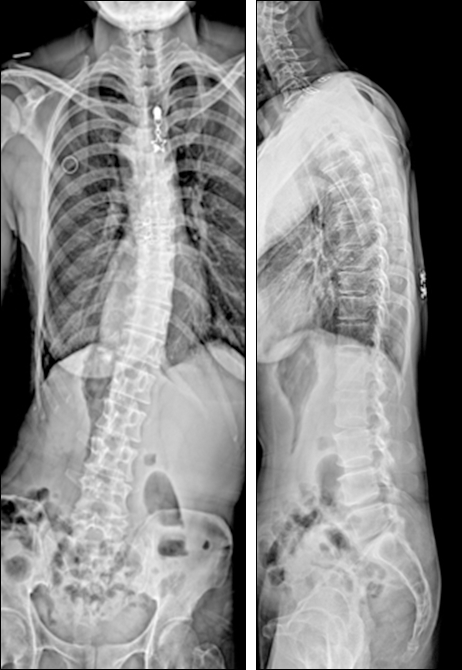

허리 통증과 우측 쏠림 보행, 구부정한 등을 교정하고자 내원한 50대 환자로,

적정회수와 간격의 도수치료로 척추측만증 교정 가능